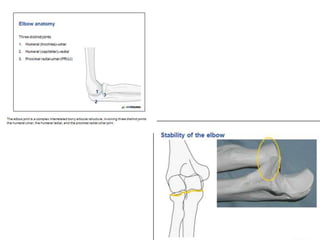

Elbow anatomy—coronoid process

• Anterior aspect of the

greater sigmoid notch

– Articulates with trochlear

– Brachialis insertion

• Laterally

– Lesser semilunar notch

articulates with radial

head

• Medially

– Attachment of anterior

fibers of MCL

Medial Collateral Ligament

Stabilizers of elbow

• Primary stabilizers

Ulnohumeral joint

MCL -( Ant. Bundle)

LCL -

• Secondary stabilizers

Radiohumeral joint

Capsule

Origin of flexor & extensor

tendons

Dynamic stabilizers - Muscle crossing elbow

Anconeus

Brachialis

Triceps

Elbow anatomy—coronoid process •Anterior aspect of the greater sigmoid notch – Articulates with trochlear – Brachialis insertion • Laterally – Lesser semilunar notch articulates with radial head • Medially – Attachment of anterior fibers of MCL

Stabilizers of elbow •Primary stabilizers Ulnohumeral joint MCL -( Ant. Bundle) LCL - • Secondary stabilizers Radiohumeral joint Capsule Origin of flexor & extensor tendons Dynamic stabilizers - Muscle crossing elbow Anconeus Brachialis Triceps